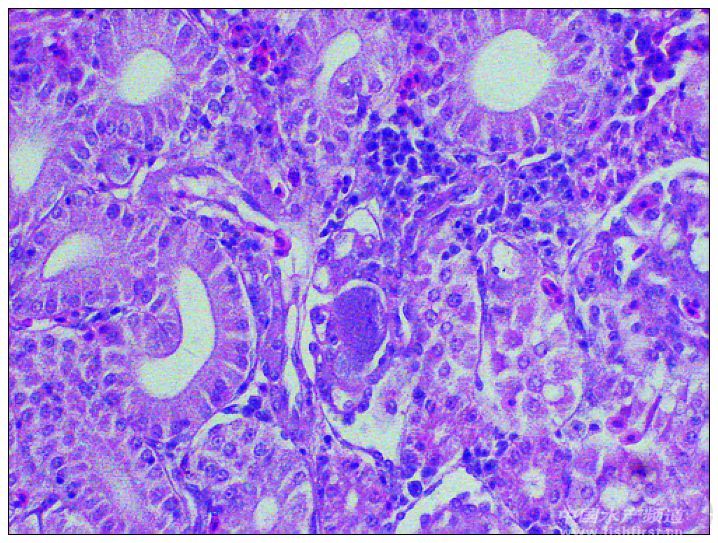

福建東山銅陵鎮一海區網箱養殖斜帶髭鯛(黑包公),網箱規格4 m×5 m,該老板共有6只網箱,每個網箱放苗2000-3000尾,投喂膨化配合顆粒飼料。(見圖1) 2012年7月下旬開始發病,發病魚外表無明顯癥狀,死亡前上浮、游水。 8月12日到現場調查,測水溫29℃,當天死亡10-20尾。從網箱中取2尾發病魚(見圖2),1尾正常魚。病魚外觀無明顯病變;內臟解剖可見發病魚脾臟明顯腫大(見圖3),胃空虛,無食(見圖4),腸道無食,發紅(圖5),其他臟器無明顯變化;正常魚無明顯異常。分別從3尾魚肝臟和腎臟接種進行細菌分離培養,并取肝臟、腎臟、脾臟和鰓等組織用PCR方法做真鯛虹彩病毒、病毒性神經壞死病毒檢測和病理組織切片觀察。 結果:從病魚的肝臟和腎臟沒接種到優勢細菌(見圖6);2尾病魚的組織器官真鯛虹彩病毒均呈陽性,正常魚鰓真鯛虹彩病毒呈陽性;3尾魚都沒檢測到病毒性神經壞死病毒;病理組織切片結果顯示病魚脾臟嚴重淤血,實質細胞輕度散在壞死,細胞稀疏,有大量各種形態的腫大細胞(見圖7),腎臟腎小球、腎小管及血管內有少量腫大細胞(見圖8),鰓有腫大細胞(見圖9),正常魚無明顯變化。 分析:本病例發病魚中各個組織器官均能檢測出真鯛虹彩病毒,正常的魚只在鰓部檢測到,并且條帶暗淡,說明沒發病的正常魚也被病毒感染,但體內病毒粒子含量低。從病理變化來看,具有真鯛虹彩病毒引起脾臟壞死、出現大量腫大細胞的致病特征,本病例發病魚死亡的原因是真鯛虹彩病毒感染引起。(文/圖 廈門利洋水產科技有限公司 利洋水產研究所 雷燕 戚瑞榮 利洋技術部 唐紹林) 圖片說明:

圖9